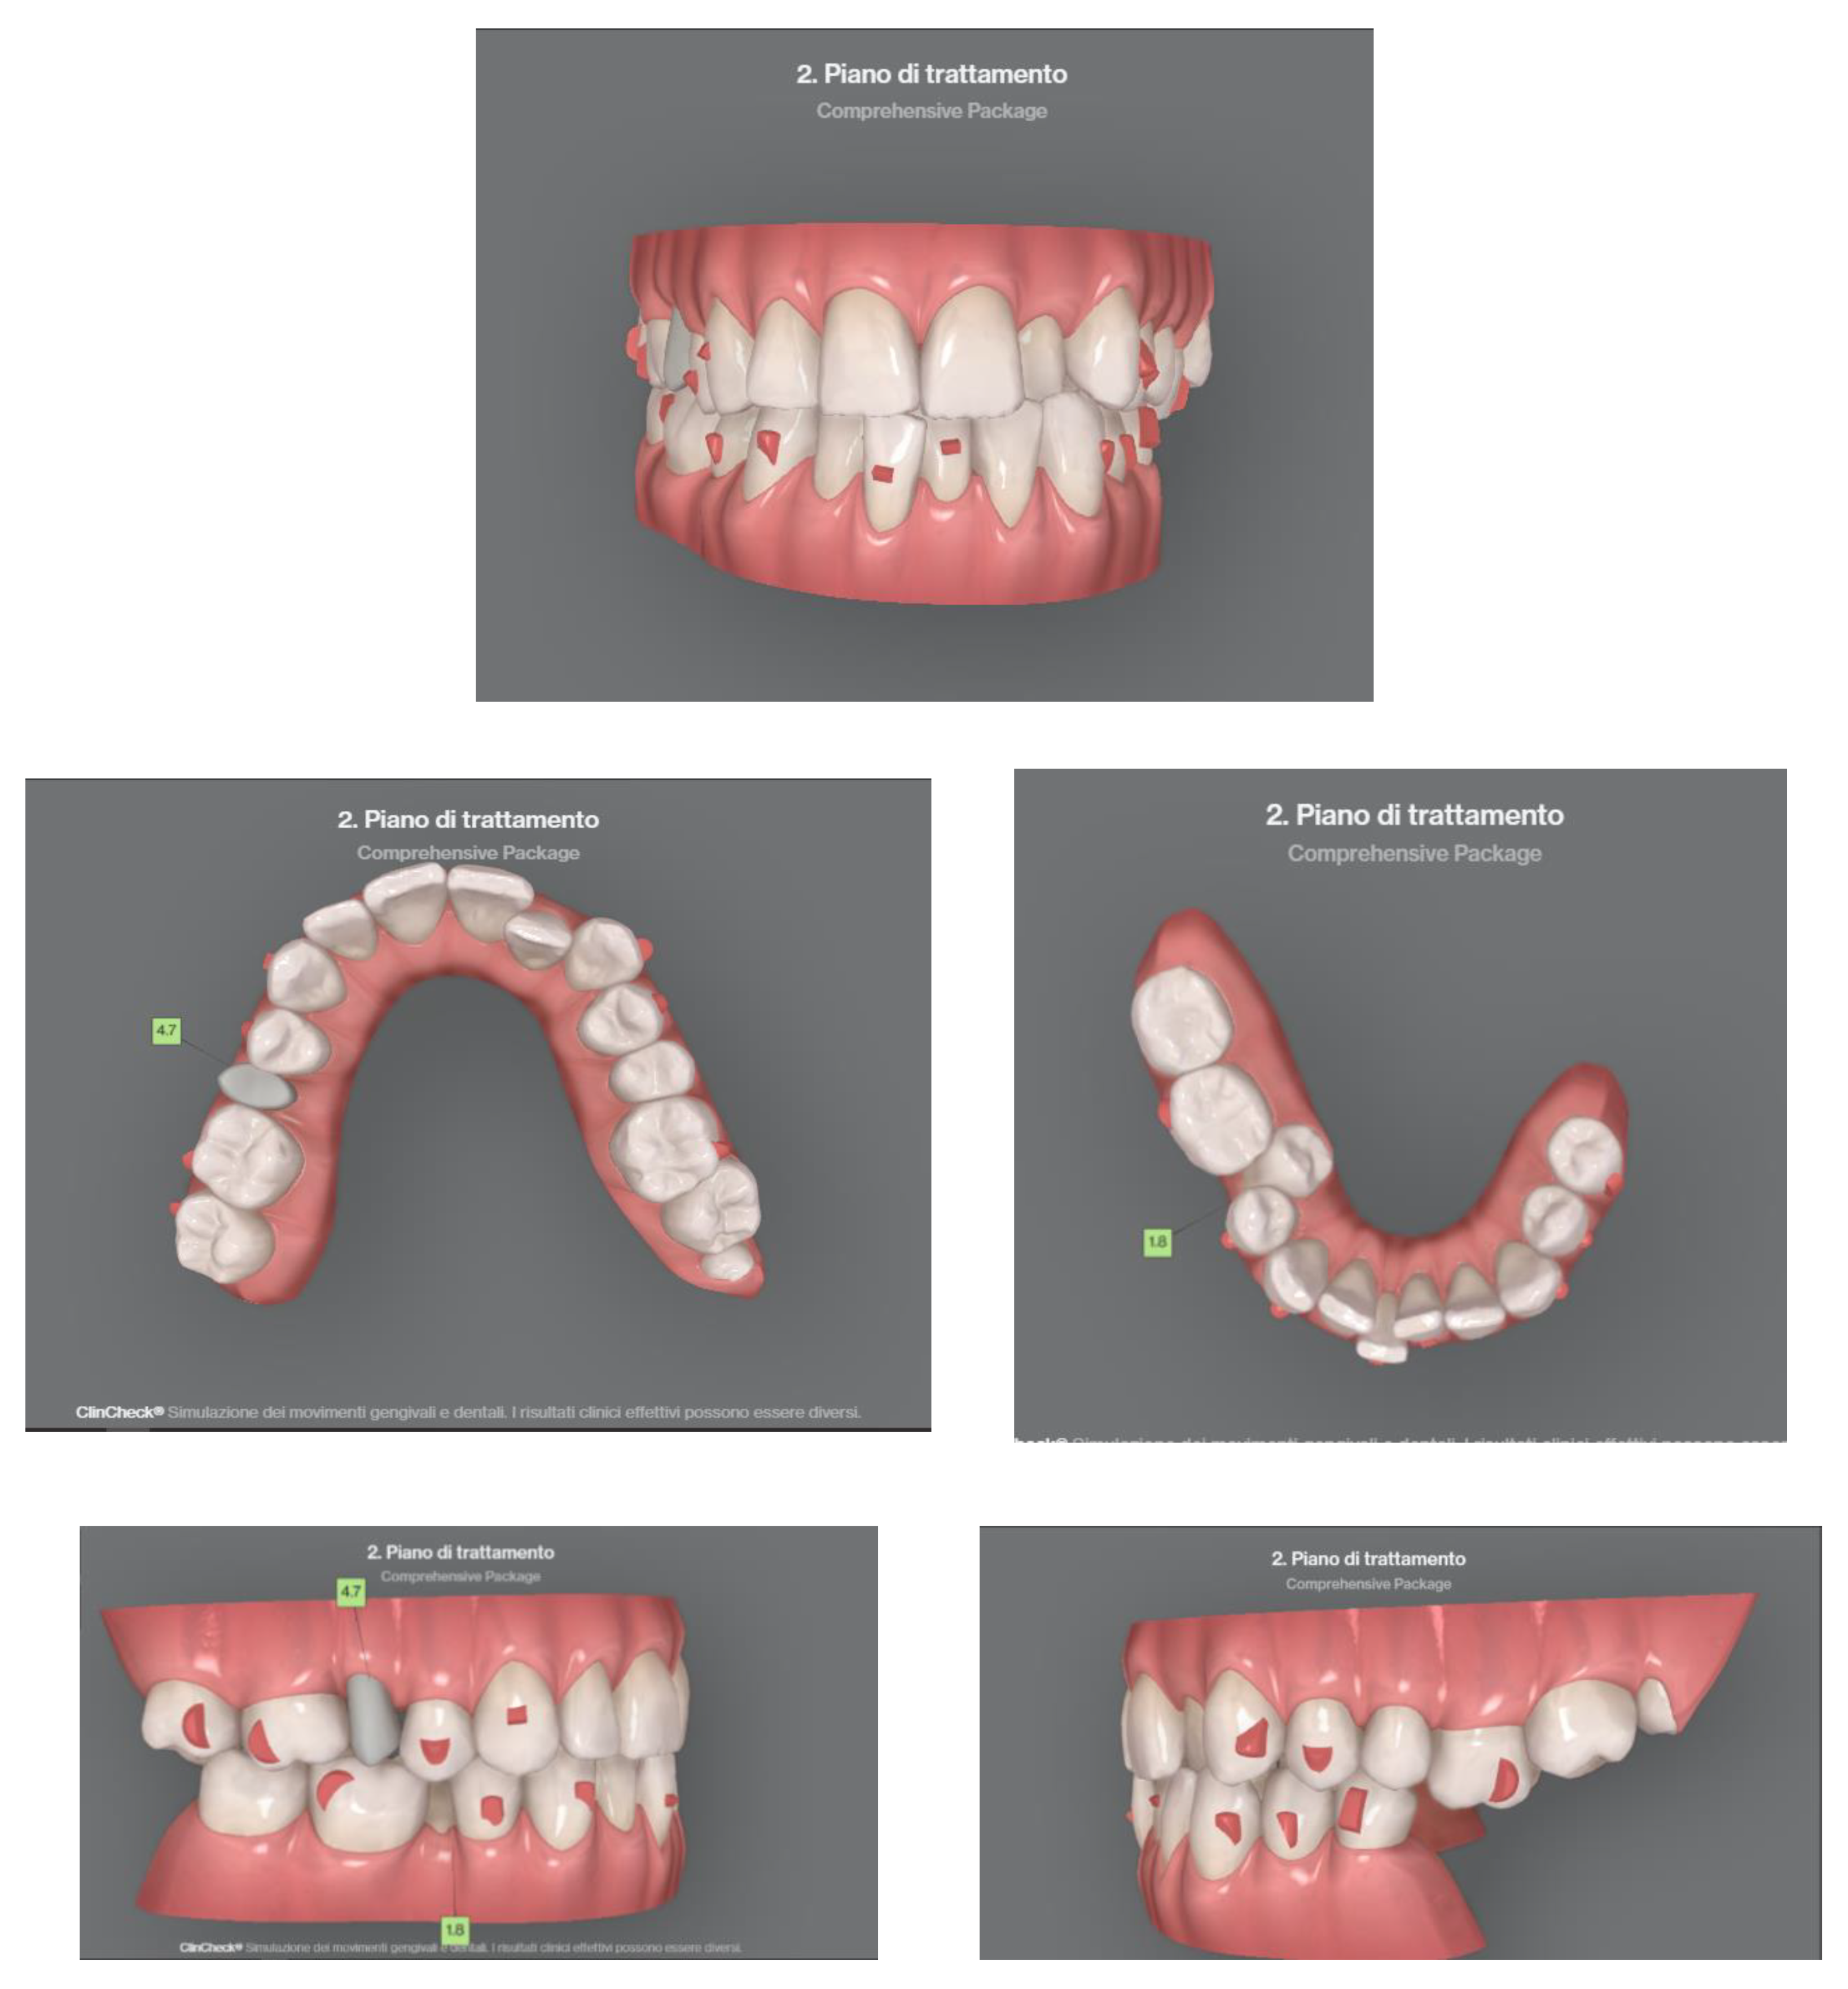

The patient is an 11-year-old female, in late mixed dentition. Clinical examination revealed acceptable oral hygiene, absence of functional anomalies and oral habits, the presence of deciduous molars (5.5 and 6.5), and erupting permanent teeth. The intraoral examination showed a molar and canine Angle class II on both sides, increased overjet, posterior unilateral functional crossbite on the right side, lower/upper midline deviated to the right/left of 2 mm, and increased overbite (5 mm) (Figure 6). The most important problem was that 1.3 was not in the arch, while the contralateral 2.3 had been present for more than 6 months. Diagnostic X-ray confirmed the 1.3 eruption delay. (Figure 7).

Figure 6. Clinical case treated with Invisalign© aligners. Intraoral views from ClinCheck. Frontal, upper, and lower occlusal and lateral view of occlusion before the beginning of treatment.